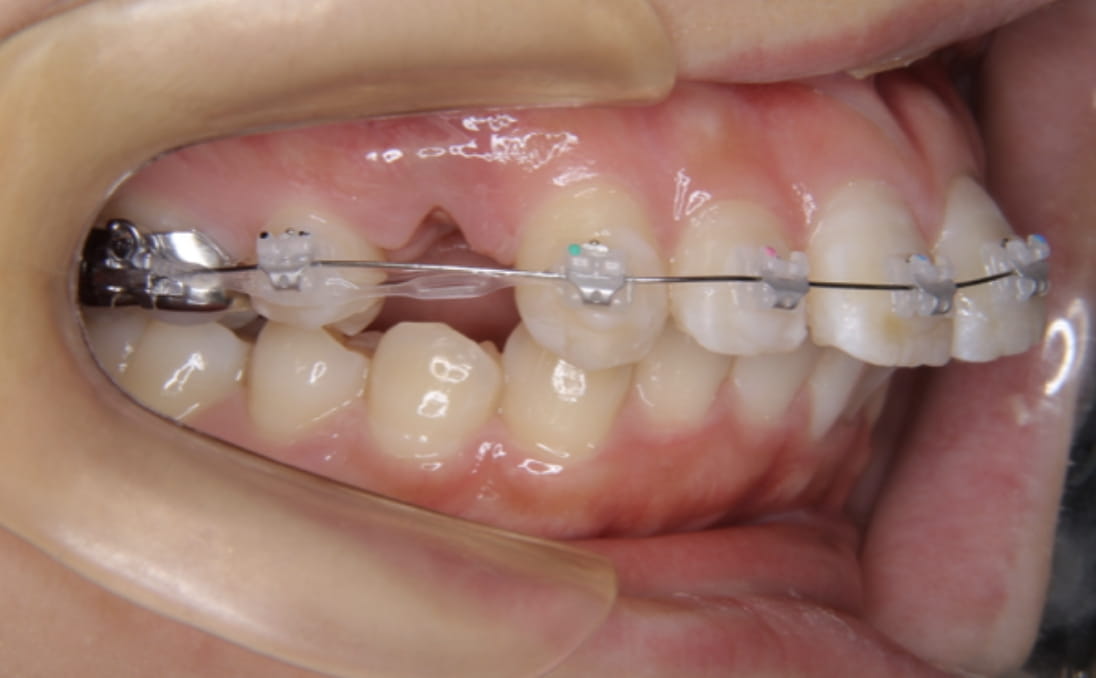

治療装置 白い表側矯正装置

抜歯 4本の抜歯

治療期間 2年2ヶ月

診断名 歯槽性上下顎前突

副作用 歯肉退縮・歯根吸収・歯髄・壊死・癒着による予期せぬ歯の動き

上下の歯の前歯の角度が傾斜しているため、抜歯が必要なケースでした。

上下の前突感を可能な限り後ろに下げました。

治療前

治療中